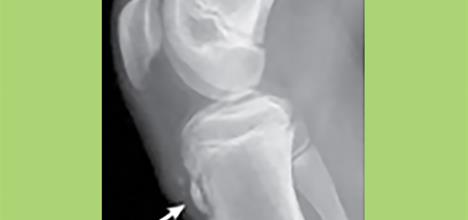

​La enfermedad de Osgood-Schlatter es una afección común entre los deportistas jóvenes; es una irritación de una placa de crecimiento en la rodilla. Suele suceder entre adolescentes activos durante sus etapas de crecimiento acelerado y se resuelve cuando el hueso deja de crecer.

Los niños tienen placas de crecimiento, llamadas apófisis, donde se unen los músculos y los tendones. El tendón rotuliano de la rodilla conecta los músculos cuádriceps (muslo) de la rótula con el hueso de la tibia en la tuberosidad tibial (el bulto que está debajo de la rodilla). Esta placa de crecimiento está unida a la tibia mediante cartílago y queda sometida a presión por sobrecarga cuando los cuádriceps tiran de ella reiteradamente al correr o saltar.